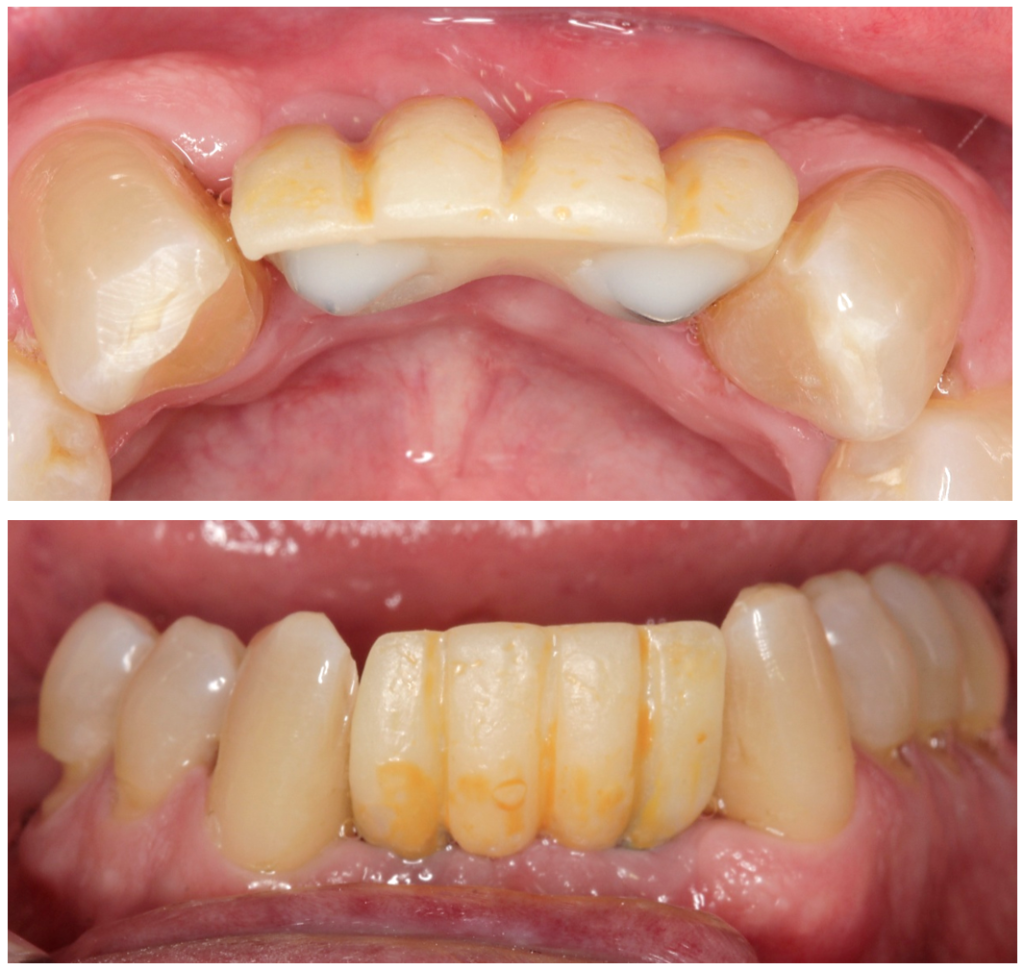

Diante do caso clínico apresentado, constatamos a importância de um correto planejamento, que evidenciou a necessidade de implantes estreitos do tipo Veloce CM e sobre esses implantes os componentes também estreitos do tipo micro-cônico para que os espaços desdentados mésio-distais fossem respeitados de forma adequada.

– em casos de espaço mésio-distal restrito podemos lançar mão de implantes estreitos do tipo Veloce de diâmetro 3.3;

– para seguir a mesma linha de raciocínio, os componentes também devem ter uma plataforma reduzida para poder assentar adequadamente a prótese sobre os implantes e o componente escolhido foi o micro-cônico.